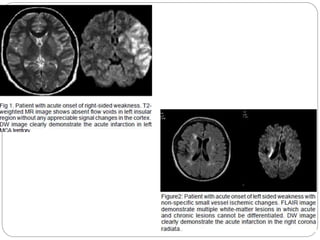

Evaluation of acute stroke on DWI

 The DWI and ADC maps show changes in

ischemic brain within minutes to few hours

 The signal intensity of acute stroke on DW

images increase during the first week after

symptom onset and decrease thereafter, but

signal remains hyper intense for a long period

(up to 72 days in the study by Lausberg et al)

 The ADC values decline rapidly after the onset

of ischemia and subsequently increase from

dark to bright 7-10 days later .

 This property may be used to differentiate the

lesion older than 10 days from more acute ones .

 Chronic infarcts are characterized by elevated

diffusion and appear hypo, iso or hyper intense

on DW images and hyperintense on ADC maps